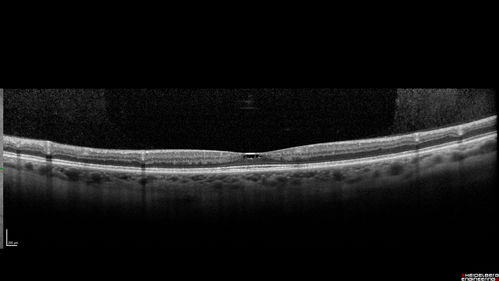

Macular Telangiectasis - Very Mild

52 year old female with normal vision and suspicious OCT referred. Multimodal imaging shows very mild mactel (loss of macular pigment, ring on multicolor image and very mild OCT findings)